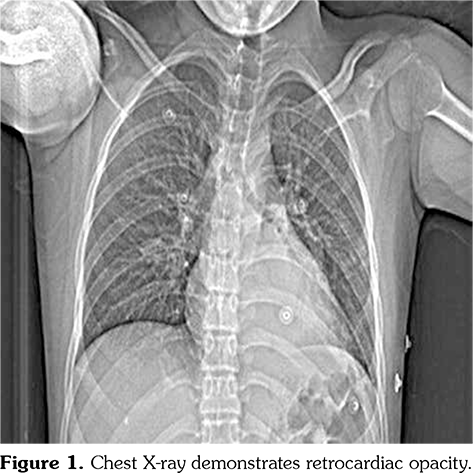

Chest X-ray showed retrocardiac hyperdensity on admission (Figure 1). Diagnostic investigations for tuberculosis were all negative. On bronchoscopy; left lower lobe bronchus was narrowed due to the external compression and abundant viscous secretions were observed. Computed tomography (CT) angiography was performed, which was consistent with multiple PAAs bilaterally (Figure 2). Diagnostic investigations such as echocardiogram and lower extremity venous Doppler ultrasonography, renal function evaluation, eye examination, abdominal ultrasound, and rheumatologic tests revealed no pathological findings. Our patient’s investigational tests for PAA were negative for cardiovascular disease, pulmonary hypertension or any infection.